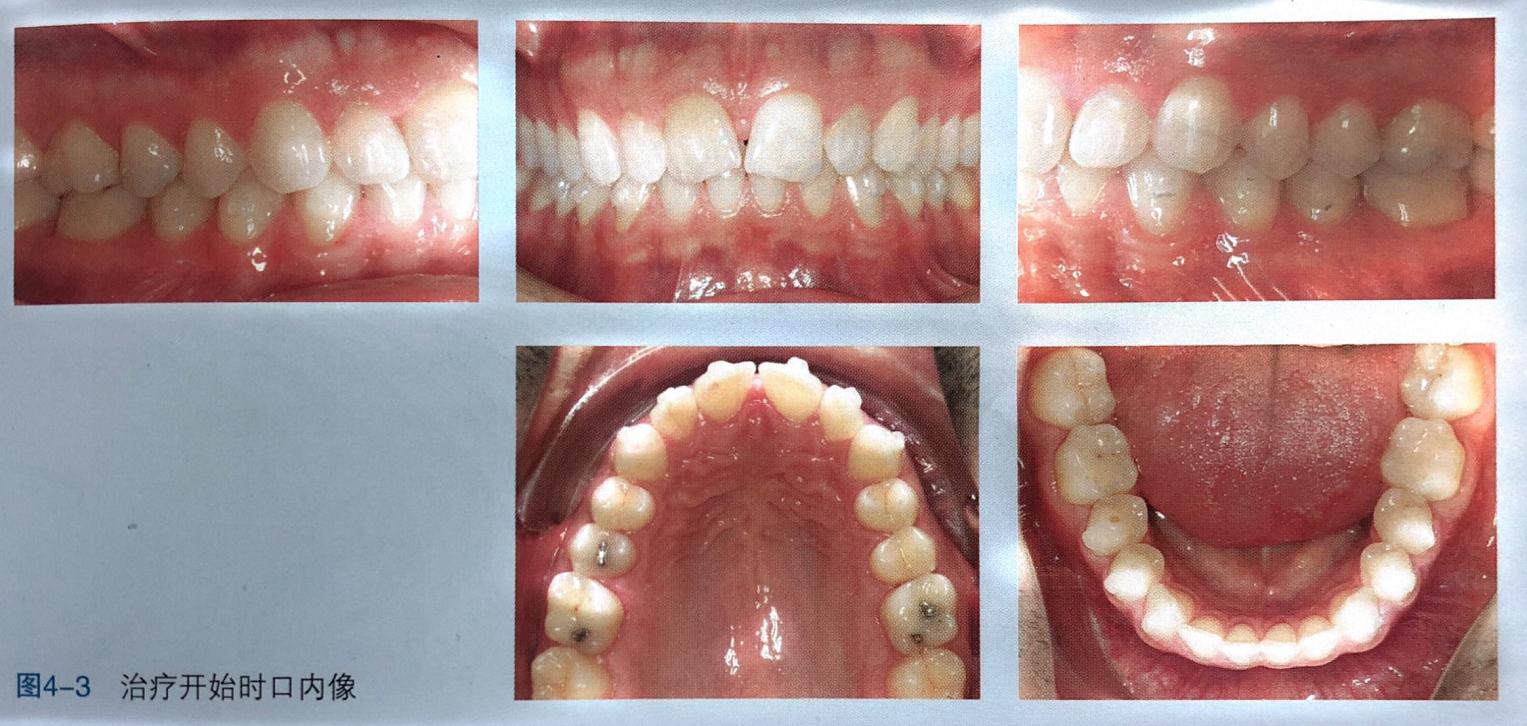

治疗前首先需要去除维持黑三角的上颌腭侧固定保持丝。治疗最初步骤之一就是正轴。为了上中切牙的正轴,两颗牙上必须使用附件(图4-2),同时近中面需要进行邻面去釉( Interpro×imalename| reduction,|PR)以使接触点往龈方移动。如果同时两颗切牙均处于扭转状态,那么需要在 Clin Check治疗方案中提出,在移动牙冠的最初就开始正轴。有了这种额外的根正轴运动,黑三角就不会进一步恶化。

另外,中切牙近中面的邻面去釉使接触点往根方移动,也会防止黑三角的发生发展。去除上颌腭侧固定保持丝,开始隐形矫治(图4-3)。附件类型为传统矩形附件,因治疗开始时尚未有G4代附件,了防止黑三角,整个治疗过程必须将两颗牙压根靠在一起。